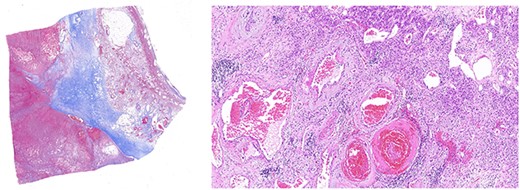

The case was discussed at a multidisciplinary meeting with the decision to advocate for an open adrenalectomy given the size and radiological findings. Intraoperatively, the lesion was 10.3 × 8.5 × 6.9 cm (Fig. 4) and weighed 319 g. Histologically, salient features of a pseudocyst were appreciated including extensive stromal fibrosis, fibrin deposition, dystrophic calcifications and areas of hyalinization, suggesting repeated previous haemorrhage and reorganization from an underlying haemangioma (Fig. 5). There were no features suggestive of a malignancy. The patient was discharged 6 days post-operatively and was well at the 8-week follow-up.

Left panel: low magnification (20×) of Masson’s trichrome stain highlighting fibrosis, fibrin and haemangioma in the adrenal cortex. Right panel: medium magnification (200×) of haematoxin- and eosin-stained section demonstrating variably dilated vascular changes filled with blood with variable hyalinization and fibrin in the wall.

Histologically, adrenal haemangiomas can be subtyped into cavernous, capillary, venous and mixed [11]. Cavernous haemangiomas have well-defined margins and are usually confined to the adrenal cortex. They exhibit numerous dilated vascular channels lined by bland endothelium, and with repeated haemorrhage can show complex necrotic, calcified, fibrotic and thrombotic changes, features compatible with reorganization (‘pseudocyst’) [12]. In our case, these features were well evident (Fig. 5).